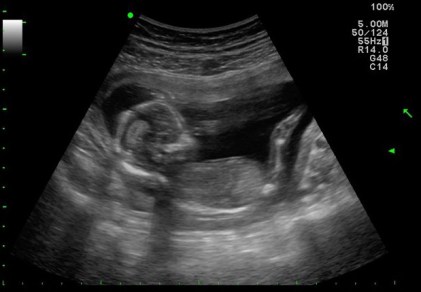

Jah at 4 months… on mummy’s birthday (2 June 2011)

While I was fortunate enough not to be plagued with horrible morning sickness, I basically had ‘whole day sickness’ till the 20th week or so which pretty much stopped me from eating most things or anything. I didn’t puke but I also didn’t feel like eating anything at all. I didn’t put on any weight in my initial months of pregnancy but thankfully Jah continued to gain weight and he was a whooping 3.6kg (based on the scans) by the time we were at 36 weeks.